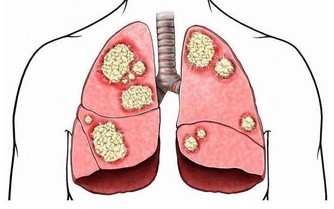

發霉食品中的黃曲霉毒素為致肝癌物質,致癌所需時間最短僅為24週,

因此食物應妥為存放,一旦發霉就應立即丟棄,

尤其是黃豆、花生、紅薯、甘蔗等,切不可再食用。